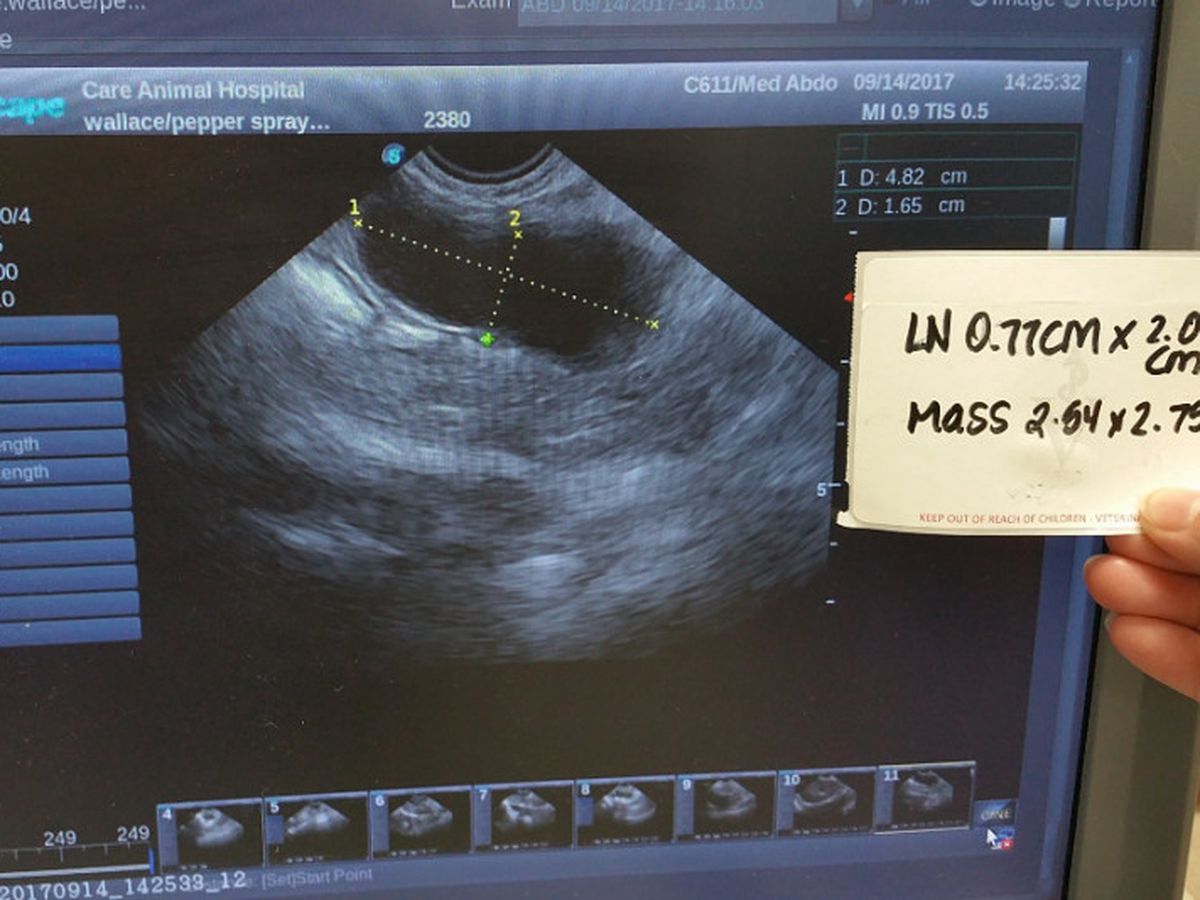

Not the best of news...My latest ultrasound shows my tumor has increased in size over the last 20 days. The note in the pic is from my original ultrasound @ Lakeshore Veterinary Specialists. This is my X ray from Lakeshore. You can see the growth that is causing my troubles. It's pushing on my colon and bladder, so it's a bit uncomfortable. Luckily I have spent many years grooming my Humans to notice and help me with such things. The meds I am taking seem to help greatly with my discomfort. Thank you all so much for your help in making them attainable. Love. Wallace...Ok, here We go...The information from my blood panel(s) is not good, in fact it's really bad. The growth in my belly that seems to be causing my intestinal problems is by all indications, malignant. That's right, cancer. My globulin/protien levels basically leave no doubt. The good Doctor estimated 3 to 6 months before I can no longer fight this. My loving Humans are doing everything in their power to make my limited time as comfortable and enjoyable as possible. As you can well imagine, this does/will involve many fairly expensive medications/tests and follow up visits to the Doc . They are also currently experiencing health problems and due to the fact that there will be absolutely no heath insurance for them untill the beginning of the calender year, this has all become overwhelming financially. Any help at all will be greatly appreciated. We are also in the process of working on some small gifts for everyone for showing so much love and support. This is a pic of me turning away from my meds. I know they are helpful, but I don't have to like taking them. We will keep you all updated as much as possible. Love. Wallace...We got some bad news from my doctor recently. The results are currenly posted on Instagram, I'll post more info here tomorrow when I can. Thank You All so much for caring. Turns out I was a bit more than just "feeling under the weather". Doc gave me a maximum of 12 hours to live without emegency procedures....And nataurally it had to be late and on a weekend. As you can well imagine, that basically doubles any fees/costs. Part2... I'm feline a bit naked without my belly fur, trying to rest comfortably...At the emrgency hospital, the good Doctor and staff #lakeshoreveterinaryspcialists were able successfully drain my bladder, externally with a needle without rupturing it. I had a large amount of fecesbacked up, so theygave me a stool softener. When the was finally inserted, there was concern. There was no evidence of the suspected crystal blockage. Once I was emptied the x rays showed an abnormal growth/mass in my abdomen that is putting pressure on colon and bladder, this is why I was unable to empty either. They suspect I also have a bladder infection due to the high white blood cell count in my urine sample.An xX-ray was taken of my lungs, they are clear. They also discovered evidence of heart diease and a heart murmur. We are waiting for culture results from the lab from samples taken last weekend at the hospital. This morning I was admitted to the great care of my primary Dr. #careanimalhospital for a 12 hour glucose scrren and blood panel testing.'m on 5 different medications now. Some of them seem to be fighting each other. Since everything affect everything else, we need to get all my different conditions and meds in synch. We will have a better understanding of my health after this current round of tets. I will post new info as it is recieved. Thank you all for your support, donations, well wishes and encouragement. I would not be here right now without it. The adventure continues....